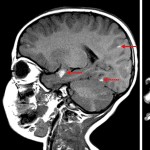

Age: 2

Sex: Female

Indication: Imbalance, large nevus on back

Meningeal melanocytosis (neurocutaneous melanosis)